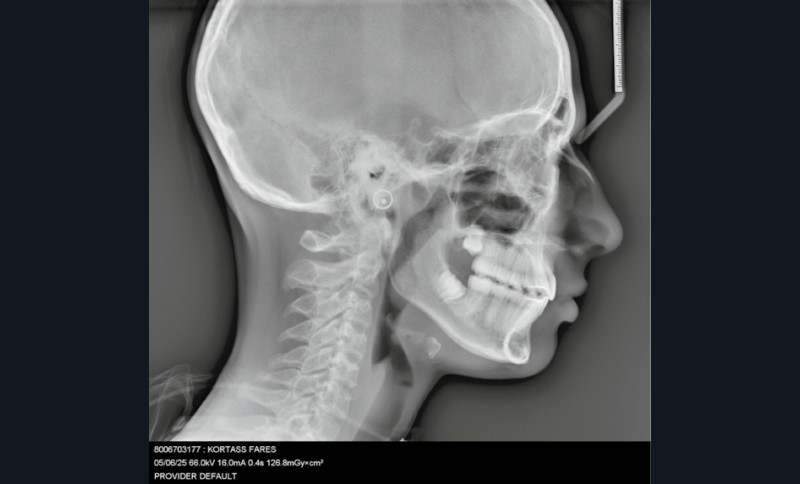

Sur le plan squelettique : Classe II, schéma hypodivergent (fig. 1c). Sur le plan fonctionnel : aucune dysfonction ni parafonction.